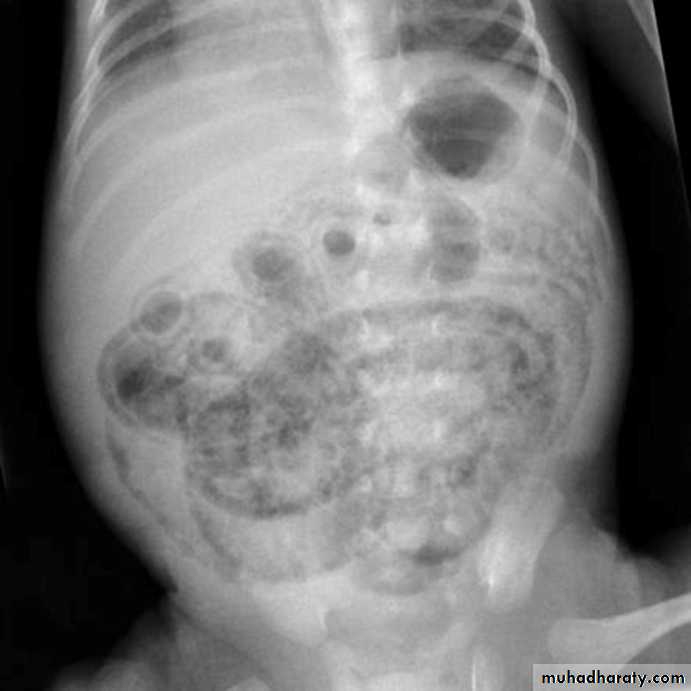

Gas in the wall of the bowel

Spherical or oval bubbles of gas are seen in wall of LB in adults in pneumatosis coli

Linear streaks of intramural gas usually indicate infarction of the bowel wall

Gas in the wall of bowel in neonates, whatever its shape, is diagnostic of necrotizing enterocolitis